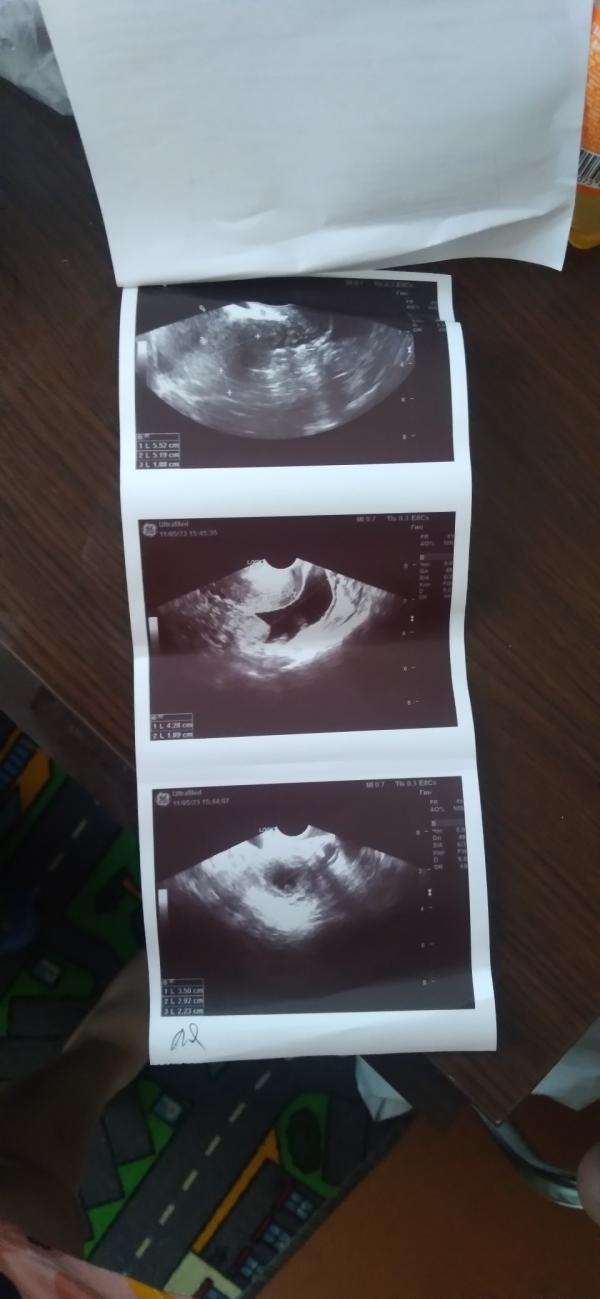

Девчонки в замешательстве пошла на узи платно . не выдержала .

Но она мне говорит что беременность она не видит но жидкость есть причём ее много . сказала что или срок маленький рано пришли или внематочная . водила трубкой сказала больно нет , я сказала нет , себя чувствую хорошо сегодня 10 день задержи отметила что беременна в календаре там показывает что 6 недель .. Но она не видит 19 на прием пойду к врачу . сказала в случаи если плохо будет вызывать скорую Но чувствую себя хорошо .. Якобы в феврале были дела в апреле не было их или календарь не правильно показывает . тест я уже вам скидывала .. Короче я в замешательстве .. У меня с сыночком тоже не видели его потом показался ..